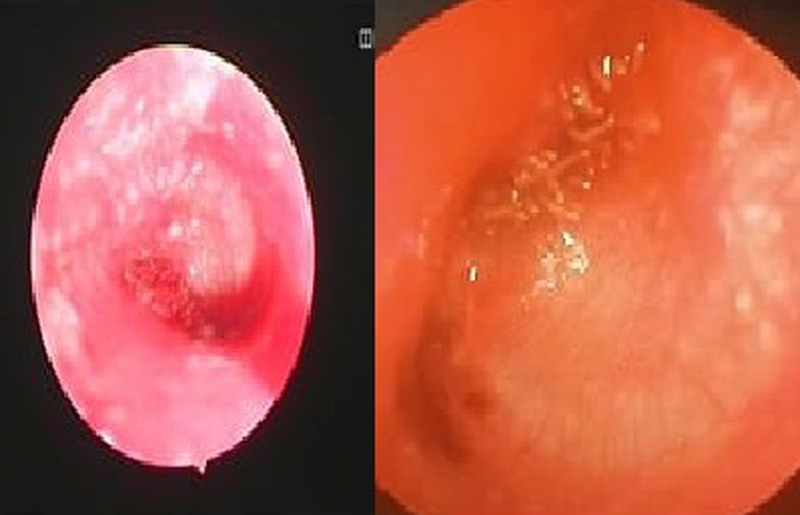

Bệnh viện Đa khoa An Phát (Tân Kỳ, Nghệ An) vừa tiếp nhận một trường hợp bệnh nhân bị dòi làm tổ trong tai.

Theo thông tin từ bệnh viện, bệnh nhân 62 tuổi (trú tại huyện Yên Thành, tỉnh Nghệ An) được đưa vào viện trong tình trạng đau và có chảy máu lỗ tai phải.

Trước đó, bệnh nhân có con nhặng xanh bay vào tai và đã được người nhà lấy ra. Tuy nhiên, mấy ngày sau, bệnh nhân xuất hiện tình trạng đau và có dịch ở tai nên đến viện kiểm tra.

Tại đây, bệnh nhân được bác sĩ chỉ định nội soi tai mũi họng, phát hiện hàng trăm con dòi (ấu trùng nhặng xanh) tại khung nhĩ trước màng nhĩ.